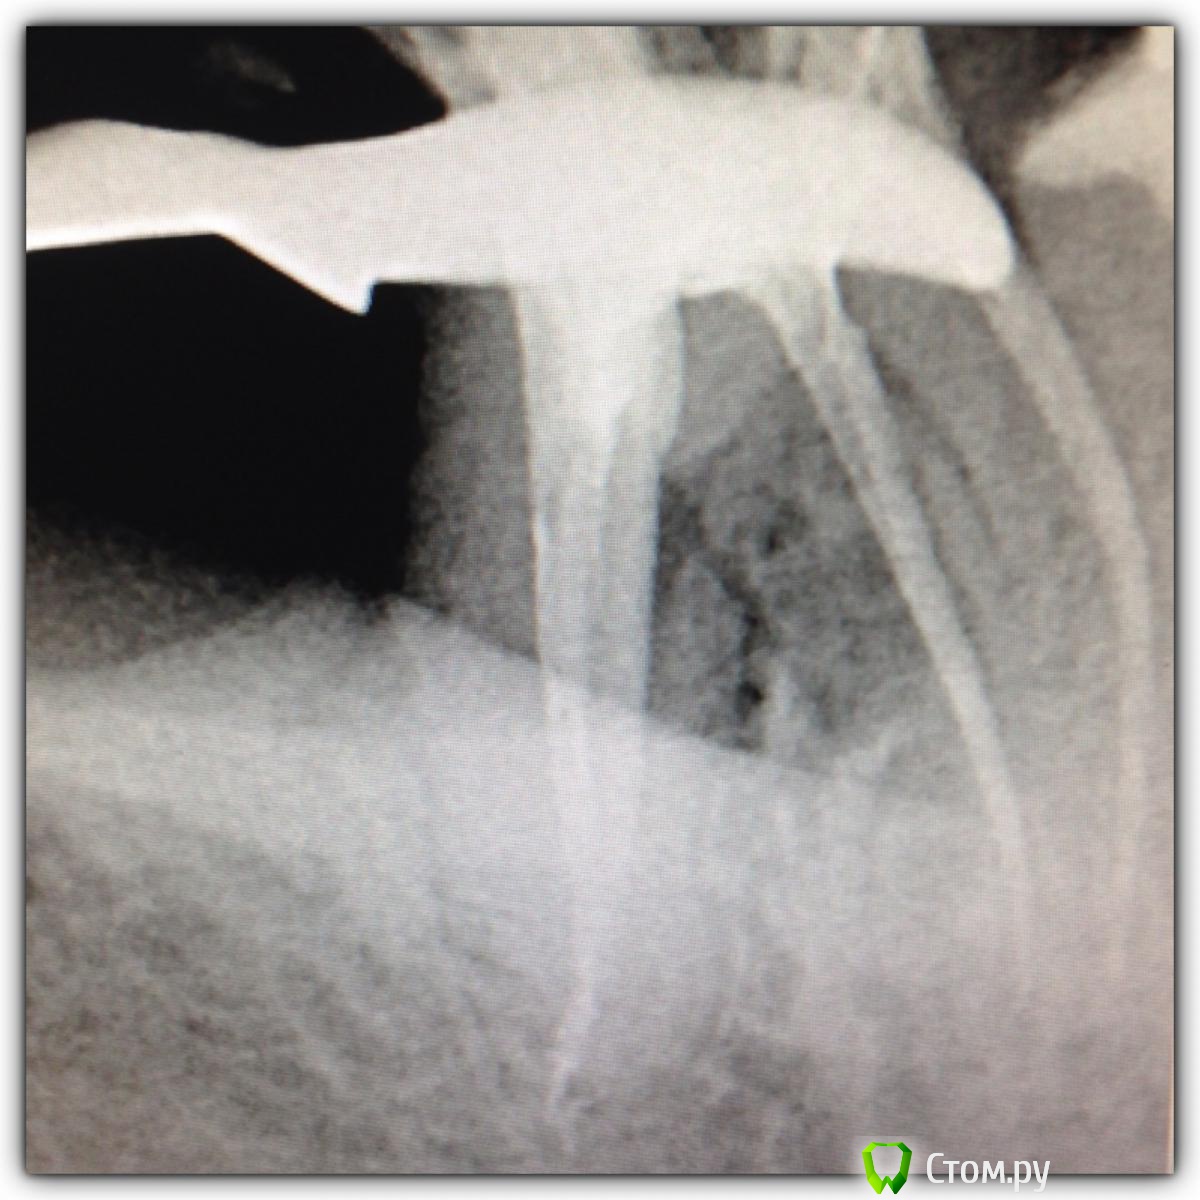

SSTi Опубликовано 9 октября, 2014 Автор Поделиться Опубликовано 9 октября, 2014 Двойка того же пациента. Тоже пошла по наклонной. Пульпит. Мш 80. Но. Апекс цел и невридим. 20ка упиралась спокойно. А мм до апекса - 80 Жаль дельта не пропаковалась. Мыл усердно 2 Ссылка на комментарий

SSTi Опубликовано 9 октября, 2014 Автор Поделиться Опубликовано 9 октября, 2014 Это канал с обратной конусностью)))) 1 Ссылка на комментарий